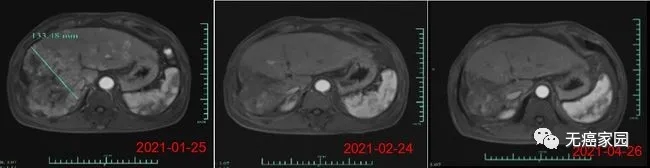

在输注CAR-T细胞后的第28天,受试者MRI结果显示最大肿瘤直径从最初的133毫米减少至9毫米,缩小超过93%。目前,该受试者正在接受CAR-T细胞输注后第3个月的评估,MRI扫描显示此肿瘤几乎消失。此外,甲胎蛋白(AFP,原发性肝癌的特定肿瘤标志物)水平从基线值 >80,000/ng/ml 下降到第1个月的1148.9ng/ml,并在第3个月下降到746.7ng/ml输注(正常范围<40ng/ml),证明 Ori-CAR-001 在晚期肝癌患者中具有显著的初步疗效。

受试者012的MRI结果示意图